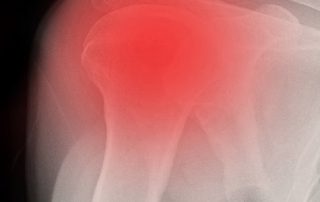

Dr. Richard Bartholomew, Shoulder Specialist2020-04-09T19:26:07+00:00New Option for Shoulder Replacement Surgery by Dr. Richard Bartholomew Reverse Total Shoulder Replacement Every year, thousands of shoulder replacements are performed in the United States to help alleviate pain and restore arm and muscle function. Some patients may have shoulder replacement surgery because they are suffering from severe arthritis [...]